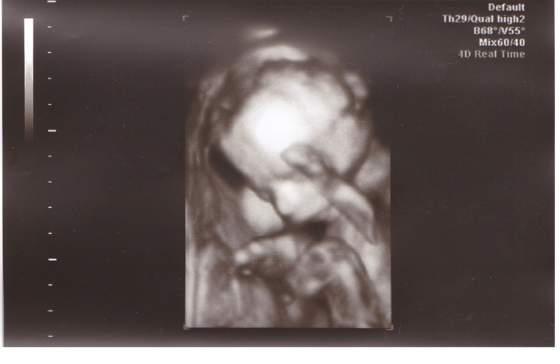

oto mója najpiękniejsza, na sto procent, córeńka:

21tyg.2.jpg21tyg.jpg

już się nie moge doczekać ubierania jej w te wszystkie śliczne rózowe ciuszki:-p